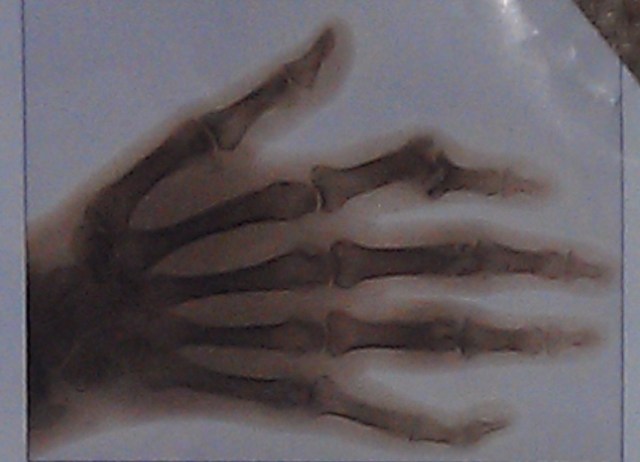

Pretty plain diagnosis

Did you know that Arthritis is both a consequence and a cause of aging? It’s true – what else can you name that can put such a kibosh on your great new health/fitness plans? Osteoarthritis alone significantly affects fully 1/3 of people over the age of 65. (cdc.gov.arthritis/basics/osteoarthritis.htm) This disease is painful both physically and mentally; it is progressive, insidious, debilitative, but it is also to an extent unnecessary.